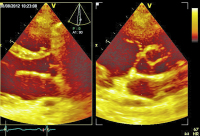

Parasternaler Längsschnitt - Parasternaler Querschnitt

Abbildung 4: Simultane Darstellung des parasternalen Längs- und Querschnittes: Die Aortenklappe imponiert am ehesten als trikuspid.